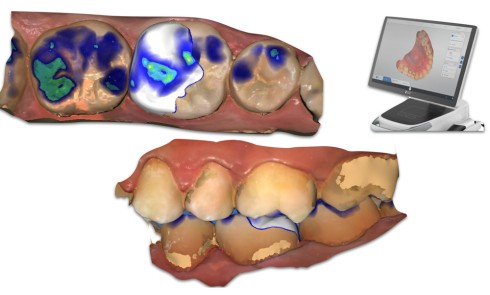

En 1985, apparaît le CEREC (CEramic REConstruction), premier système de CFAO directe (ou chairside) destiné au cabinet dentaire, permettant de...Empreinte numérique ou conventionnelle en prothèse fixée Faible, moyenne et grande étendue

En quelques années, les flux de travail se sont numérisés, modernisés, réinventés grâce aux avancées technologiques (matérielles et logicielles), mais...Réhabilitations complètes implanto-portées et flux numérique